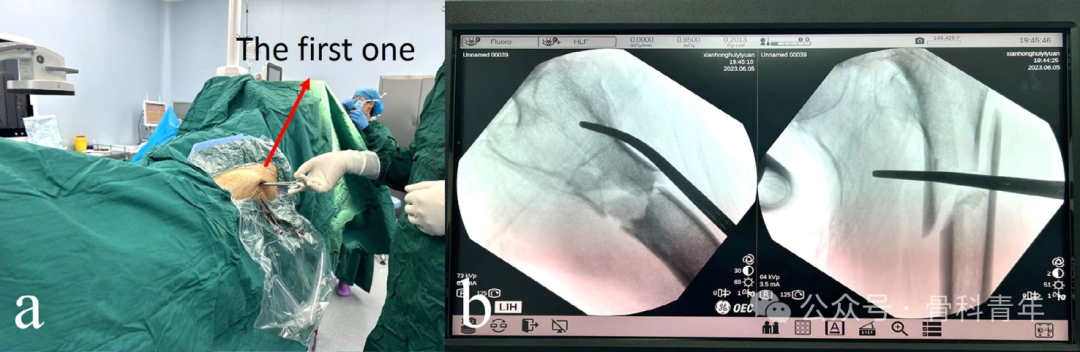

在透视引导下,自骨折线上方1cm,股骨中线偏后1cm作小切口,将血管钳紧贴股骨前方骨皮质置入,并插入内侧肌肉中,后上提血管钳,将股骨近端往下按压,复位屈曲的股骨近端:

与屈曲畸形的复位类似,屈曲畸形为冠状位上采用血管钳复位,外展畸形为在矢状面上复位。在骨折线近端1cm,股骨前方轴线内侧1cm处作小切口,依同法置入血管钳,贴于股骨近端外侧皮质置入,复位外展的股骨近端。如单血管钳复位困难,可置入第2把血管钳: